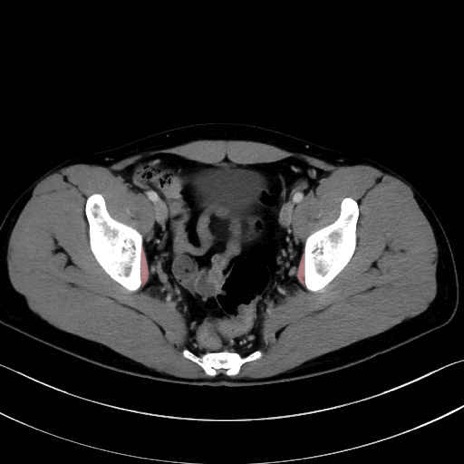

内閉鎖筋(obturator internus) のCT画像の解剖

内閉鎖筋 (Obturator internus)